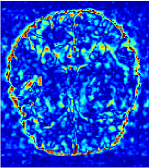

Qualitative comparison between conventional and Meta-learning methods are shown in Figure 1 and 3, which display the reconstructed MR images of the same slice for T1 and T2 respectively, we label the zoomed-in details of HGG in the red boxes. We observe the evidence that conventional learning is more blurry and lost sharp edges, especially in lower CS ratios. From the point-wise error map, we find meta-learning has the ability to reduce noises especially in some detailed and complicated regions comparing to conventional learning.

In this section, we test the generalizability of the proposed model that tests on unseen tasks. We fix the well-trained task-invariant parameter and only train for sampling ratios 15%, 25% and 35% with radio masks and sampling ratios 10%, 20%, 30% and 40% with Cartesian masks. In this experiment, we only used 100 training data for each CS ratio and apply a total of 50 epochs. The averaged evaluation values and standard deviations are listed in Table 5.4 and 5.4 for reconstructed T1 and T2 brain images respectively that proceed with radio masks, and Table 5.4 shows the qualitative performance for reconstructed T2 brain image that applied random Cartesian sampling masks. In T1 image reconstruction results, meta-learning improved 1.6921 dB in PSNR for 15% CS ratio, 1.6608 dB for 25% CS ratio, and 0.5764 dB for 35% comparing to the conventional method, which in the tendency that the level of reconstruction quality for lower CS ratios improved more than higher CS ratios. A similar trend happens in T2 reconstruction results with different sampling masks. The qualitative comparisons are illustrated in Figure 2, 4 and 5 for T1 and T2 images tested in skewed CS ratios in radio masks, and T2 images tested in Cartesian masks with regular CS ratios respectively. In the experiments that conducted with radio masks, meta-learning is superior to conventional learning especially at CS ratio 15%, one can observe that the detailed region in red boxes keeps edges and is more close to the true image, while conventional method reconstructions are hazier and lost details in some complicated tissue. The point-wise error map also indicates that Meta-learning has the ability to suppress noises.